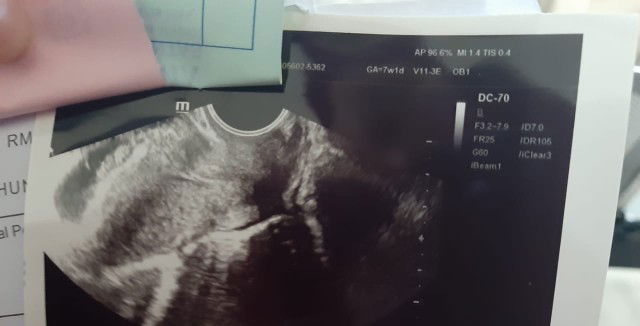

pendarahan kelahamilan 7 minggu

Halo bun, Saya mau sharing sekaligus bertanya. Saat ini saya sdg hamil 7 minggu, lalu tgl 7 juli mengalami pendarahan warna merah dan encer kemudia saya lngsung dibawa ke igd, diperiksa sama bidan RS Alhamdulillah ga ada pembukaan, lalu di usg oleh dokter spog nya Alhamdulillah kantung dan janinnya msh dlm keadaan normal. Saya diberikan obt penguat yg diminum dan di masukan ke dlm vagina. Alhamdulillah darah merahnya udh ga keluar lg, cuma yg keluar kaya flek warna coklat gtu saat ini sdh 2 hari, tiap kali perut saya tertekan entah itu krn ketawa, atau uwek2 krn enek psti keluar fleknya. Ada ga yg prnh ngalamin kaya saya? Dan apakah kehamilannya bisa sehat kembali lalu selamat? Saya sdg bedrest smpai waktu yg blm ditentukan. Ini saya lampirkan foto usgnya